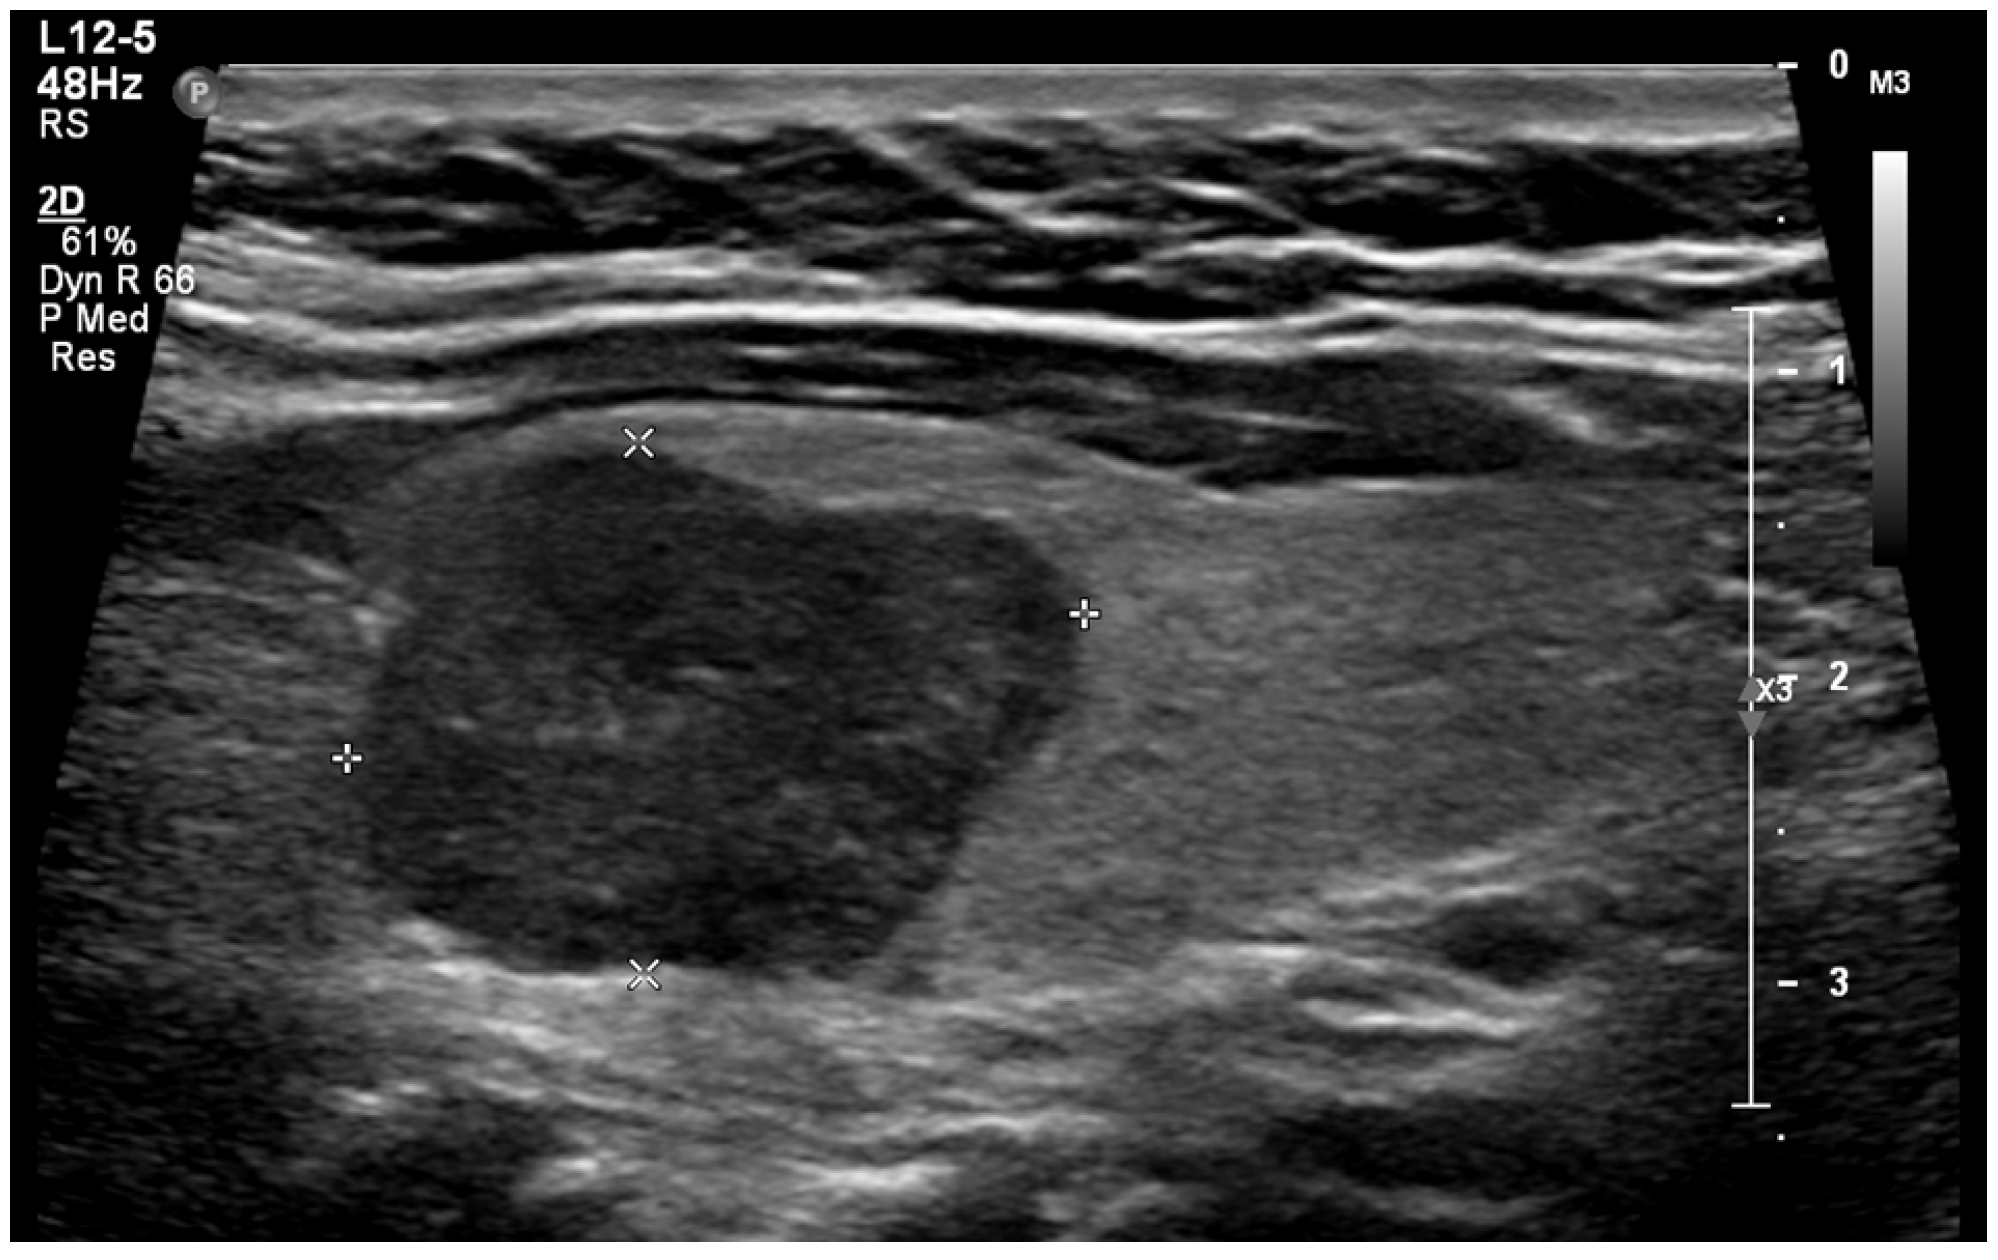

When a thyroid nodule has an anteroposterior (AP) dimension that exceeds its transverse (TR) dimension such that the ratio is greater than 1, it is classified as having a taller-than-wide shape (Figure 3). This observation was first reported in 2002 by Kim et al. in a study involving 155 thyroid nodules with an average size of 7.5 mm, of which 49 were malignant. This study found that a taller-than-wide shape was associated with a 92.5% specificity and 32.7% sensitivity for malignancy [51]. The authors proposed that this taller-than-wide configuration may reflect an underlying tendency for malignant nodules to grow across tissue planes, unlike benign nodules, that grow along tissue planes [51]. A meta-analysis and a systematic review by Brito et al., examining 31 studies and 18,288 nodules with an average size of 1.5 cm, reported that a taller-than-wide shape was associated with an OR of 11.1 (95% CI, 6.6 to 18.9) for malignancy [52]. In our study, we observed a significant association between a taller-than-wide shape and malignancy for nodules <1 cm but not for those above this size. For nodules <1 cm, a taller-than-wide shape was observed in 66.7% of malignant nodules compared to 5% of benign nodules (p = 0.03). In comparison, for nodules ≥1 cm, a taller-than-wide shape was seen in 14.6% of malignant nodules versus 13% of benign nodules (p = 0.67). Other studies have found similar findings [53,54]. In a study involving 207 nodules, of which 110 were malignant, Ren et al. found that a taller-than-wide shape was a good predictor for papillary cancer for nodules ≤1 cm but not for larger nodules [53]. In a study involving 1238 nodules, of which 159 were papillary cancers, Kim et al. found that a taller-than-wide shape was associated with an OR for cancer of 2.7 (95% CI, 1.7 to 4.3) (p < 0.001) for nodules ≤1 cm vs. an OR of 1.2 (95% CI, 0.4 to 3.2) (p = 0.77) for nodules >1 cm [54].

Figure 3. A benign nodule with a taller-than-wide shape.